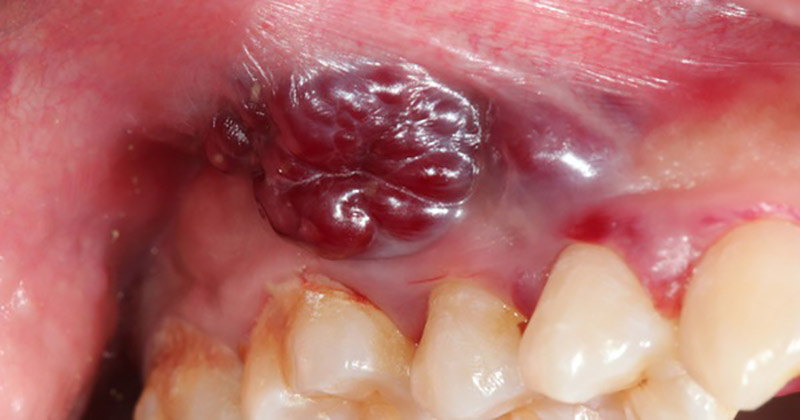

Nhiệt miệng, gây lở loét trong khoang miệng là tình trạng rất phổ biến, ảnh hưởng đến mọi người ở mọi lứa tuổi. Tuy nhiên, sự xuất hiện của chứng nhiệt miệng màu đen khiến nhiều người lo ngại về nguyên nhân cũng như những tác động tiềm ẩn của chúng.

Thông thường, các vết loét do nhiệt miệng sẽ có màu vàng đục hoặc trắng ngà. Tuy nhiên, có những trường hợp xuất hiện vết loét nhiệt miệng màu đen. Nếu gặp phải tình trạng này, bạn cần chú ý theo dõi, đồng thời đi khám bác sĩ sớm để được chẩn đoán và điều trị phù hợp.

Trong khi các vết loét nhiệt miệng thông thường có màu sắc đặc trưng là màu trắng ngà hoặc vàng đục, thì sự xuất hiện của các vết loét nhiệt miệng màu đen đòi hỏi chúng ta phải cảnh giác và có sự chăm sóc y tế kịp thời. Đáng chú ý, nếu vết loét nhiệt miệng màu đen có kèm theo chảy máu thì bạn nên đi khám sớm để xác định nguyên nhân. Nhiều khả năng nhiệt miệng màu đen là dấu hiệu cảnh báo bệnh lý nguy hiểm, bao gồm nguy cơ ung thư lưỡi.

Các vết loét nhiệt miệng nói chung, nhiệt miệng màu đen nói riêng xuất hiện trên niêm mạc lưỡi cần được theo dõi thận trọng vì chúng có thể cảnh báo hiệu một tình trạng tiềm ẩn như ung thư lưỡi. Để giúp phát hiện kịp thời và tối ưu hóa kết quả điều trị, điều quan trọng là bạn phải nhận biết được các dấu hiệu cần gặp bác sĩ ngay lập tức.

Các vết lở nhiệt miệng màu đen kèm theo đau, chảy máu và có mủ trắng hoặc vàng có thể là cảnh báo tình trạng sức khỏe tiềm ẩn và cần được bác sĩ thăm khám và điều trị ngay.

Nếu kích thước của vết loét tăng lên theo thời gian, dẫn đến hình thành khối u, cục cứng, xơ hóa hoặc dính vào niêm mạc lưỡi, bạn cần phải được chăm sóc y tế kịp thời để đánh giá khả năng mắc bệnh ác tính.